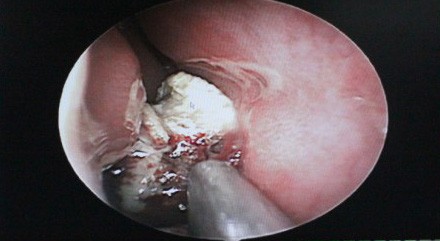

鼻内镜下发现徐小姐右鼻腔内有未知脓肿物存在

经过全面的检查并取得了小徐本人的同意后,医生决定为小徐实施手术。1月5日,手术开始。西安中大耳鼻喉医院耳鼻喉科副主任医师来长荣黄主任在局麻鼻内镜下为小徐进行了右鼻腔肿物切除术,手术中终于见到了那个未知的脓肿,竟然是一块直径约2cm的橡皮异物,由于时间太长,橡皮表面钙化结晶盐形成,堵塞在了下鼻道和鼻中隔之间。在鼻内镜下去除异物之后,黄主任又进行了右侧筛窦开放、蝶窦口扩大术,清理了蝶窦腔内囊肿, 后以明胶海绵填塞右侧鼻腔,手术顺利完成。